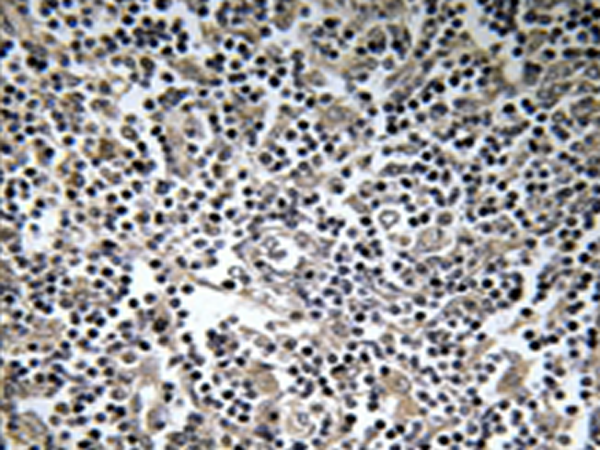

IHC positive control:

Human lymph noe tissue

IHC Recommend dilution:

50-100